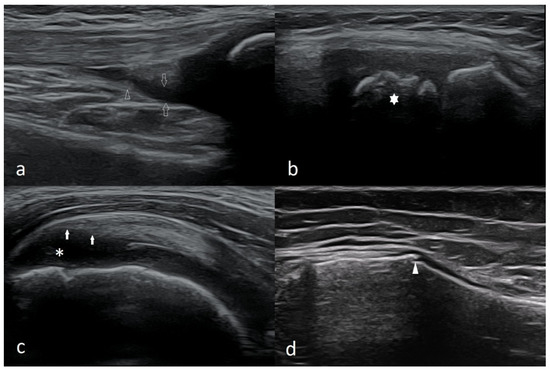

3.2.2. Osgood–Schlatter Disease

3.2.3. Ligament Injuries